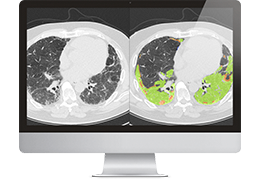

ART-Plan™ Artificial Intelligence Contouring